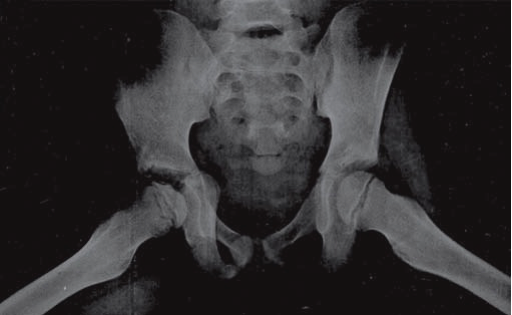

Avascular Necrosis

- Avascular necrosis of bone occurs secondary to vaso-occlusion of nutrient artery. Femoral head, humerus, upper-third of tibia can be affected, but weight bearing makes femoral head necrosis more likely to cause severe disability.